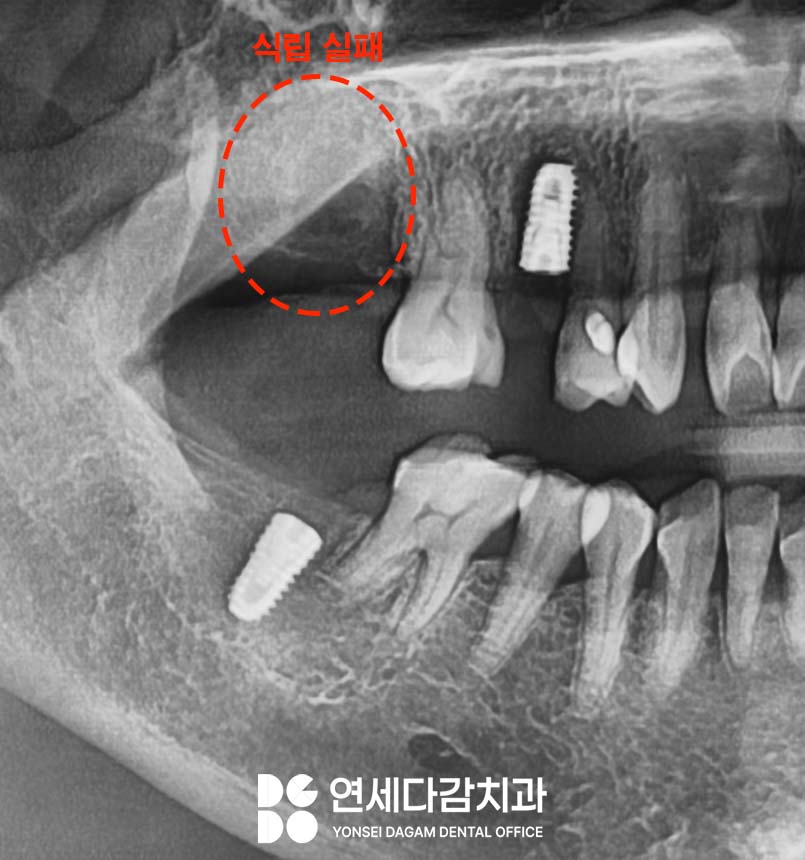

첫 번째 수술이 실패한 후,

고정력을 향상시키기 위해

더 두꺼운 직경의 고정체(fixture)를

사용해 재시도했으나

역시나 고정력을 얻지 못했습니다.